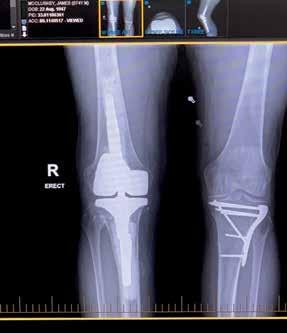

1. The forklift and safe at the scene of the accident.

2. Sergeant Rod Parsons and Senior Constable Rick Jones visit McCluskey in hospital.

3-4. X-rays showing screws and plates in McCluskey’s legs.

McCluskey would remain in hospital for four weeks and, in that time, undergo four operations. He wound up with rods, plates and screws in his legs and a skin graft. In his right leg alone were three plates and 29 screws

So, there was McCluskey, trapped under the monstrous size and weight of the safe with a compound fracture of his right tibia Indeed, the broken bone had pierced through his skin and was sticking clean out of his leg

A break to his left tibia was slightly less dramatic to the eye as the bone had not likewise pierced its way out of his leg.